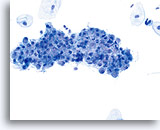

Benign Appearing Endometrial Cells

Endometrial cells may display a wide range of nuclear and cytoplasmic size, as well as architectural configuration. Endometrial cell groups tend to round up in ThinPrep solution. The nuclei are well preserved and appear crisp with distinct, active chromatin; chromocenters are frequently noted.

Bethesda 2014 recommends the reporting of benign appearing exfoliated endometrial cells in women age 45 and above, regardless of clinical history. The general categorization “Other” was included in the Bethesda 2001 lexicon for this purpose. Histiocytes, stromal cells and abraded endometrial cells do not have the same significance as exfoliated endometrial cells and should not be considered in the same context. While most often benign, identification of endometrial cells, particularly if not associated with menses or after menopause, may indicate risk for an endometrial abnormality.